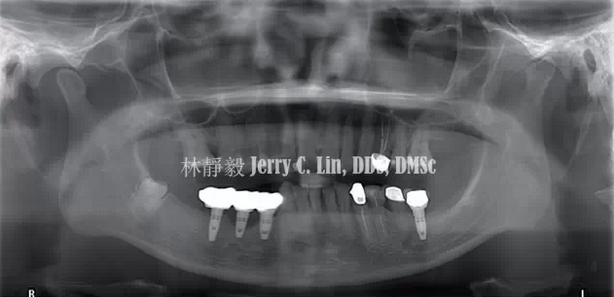

嚴(yán)重種植體周圍炎的處理(二)——林靜毅醫(yī)師